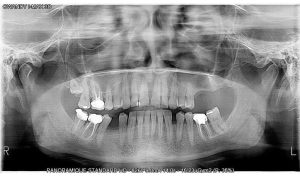

EXCEPTIONAL IMAGE QUALITY

You’ll be able to view all clinical and anatomical details with maximum precision.

Specially adapted programmes

The I-Max features a wide range of programmes that can be used for any type of examination your practice requires (child / adult).

Incorporating ALI-S (Automatic Layers Integration System), the unit directly and automatically selects the best sections in order to display a perfect image, without any form of operator involvement.

24 2D programmes to make your medical diagnostics easier.